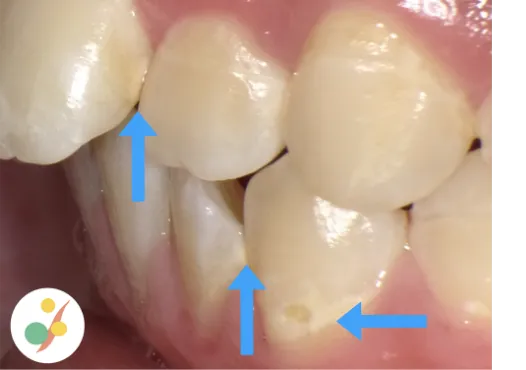

親知らずは真っ直ぐ生えていることはあまりありません。そのため汚れが溜まりやすく、写真の様に隣の歯に大きな虫歯を作ってしまいお口の環境にい大きく影響を与えてしまうこともあるため、問題を起こしそうな場合は抜歯を勧めています。